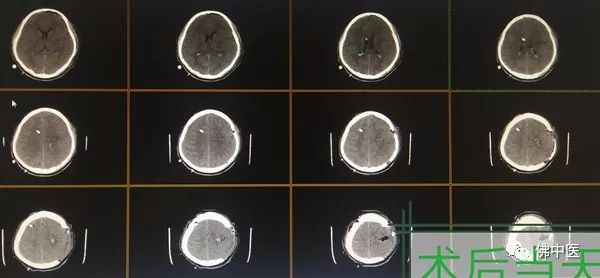

小刘的意识障碍在短时间内逐步加深,病情进展迅速。行头颅CT显示:左颞顶叶大量脑出血,血肿破入脑室,形成脑室铸型。颅内血肿巨大且脑脊液循环通路严重受阻,病情危殆!

术前CT